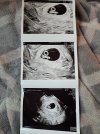

Na pierwszej wizycie serduszka widać nie było, na drugiej 6+3 już było a tu mam aktualizację z dzisiaj 6+6. Wgl babka, u której myslalam, że będę ciaze prowadzić bo prowadziła nas w diagnostyce niepłodności powiedziala nam dzisiaj, ze jak mamy możliwość prowadzić gdzie indziej to żebyśmy sobie prowadzili bo u nich jednak za każdą wizytę trzeba płacić a ona jest w sumie specjalistą od nieplodnosci. Więc chyba jednak bede prowadzić ciążę w luxmedzie. W sumie piątkowa wizyta była spoko, dzisiaj sobie tam badania zrobiłam. Będzie chociaż trochę lżej finansowoJa tylko tak zapytam - w którym tyg szlyście na pierwszą wizytę? Były serduszka już wtedy? Ja to zawsze mam tak, jakbym pierwsze dziecko miaładalej nic nie wiem